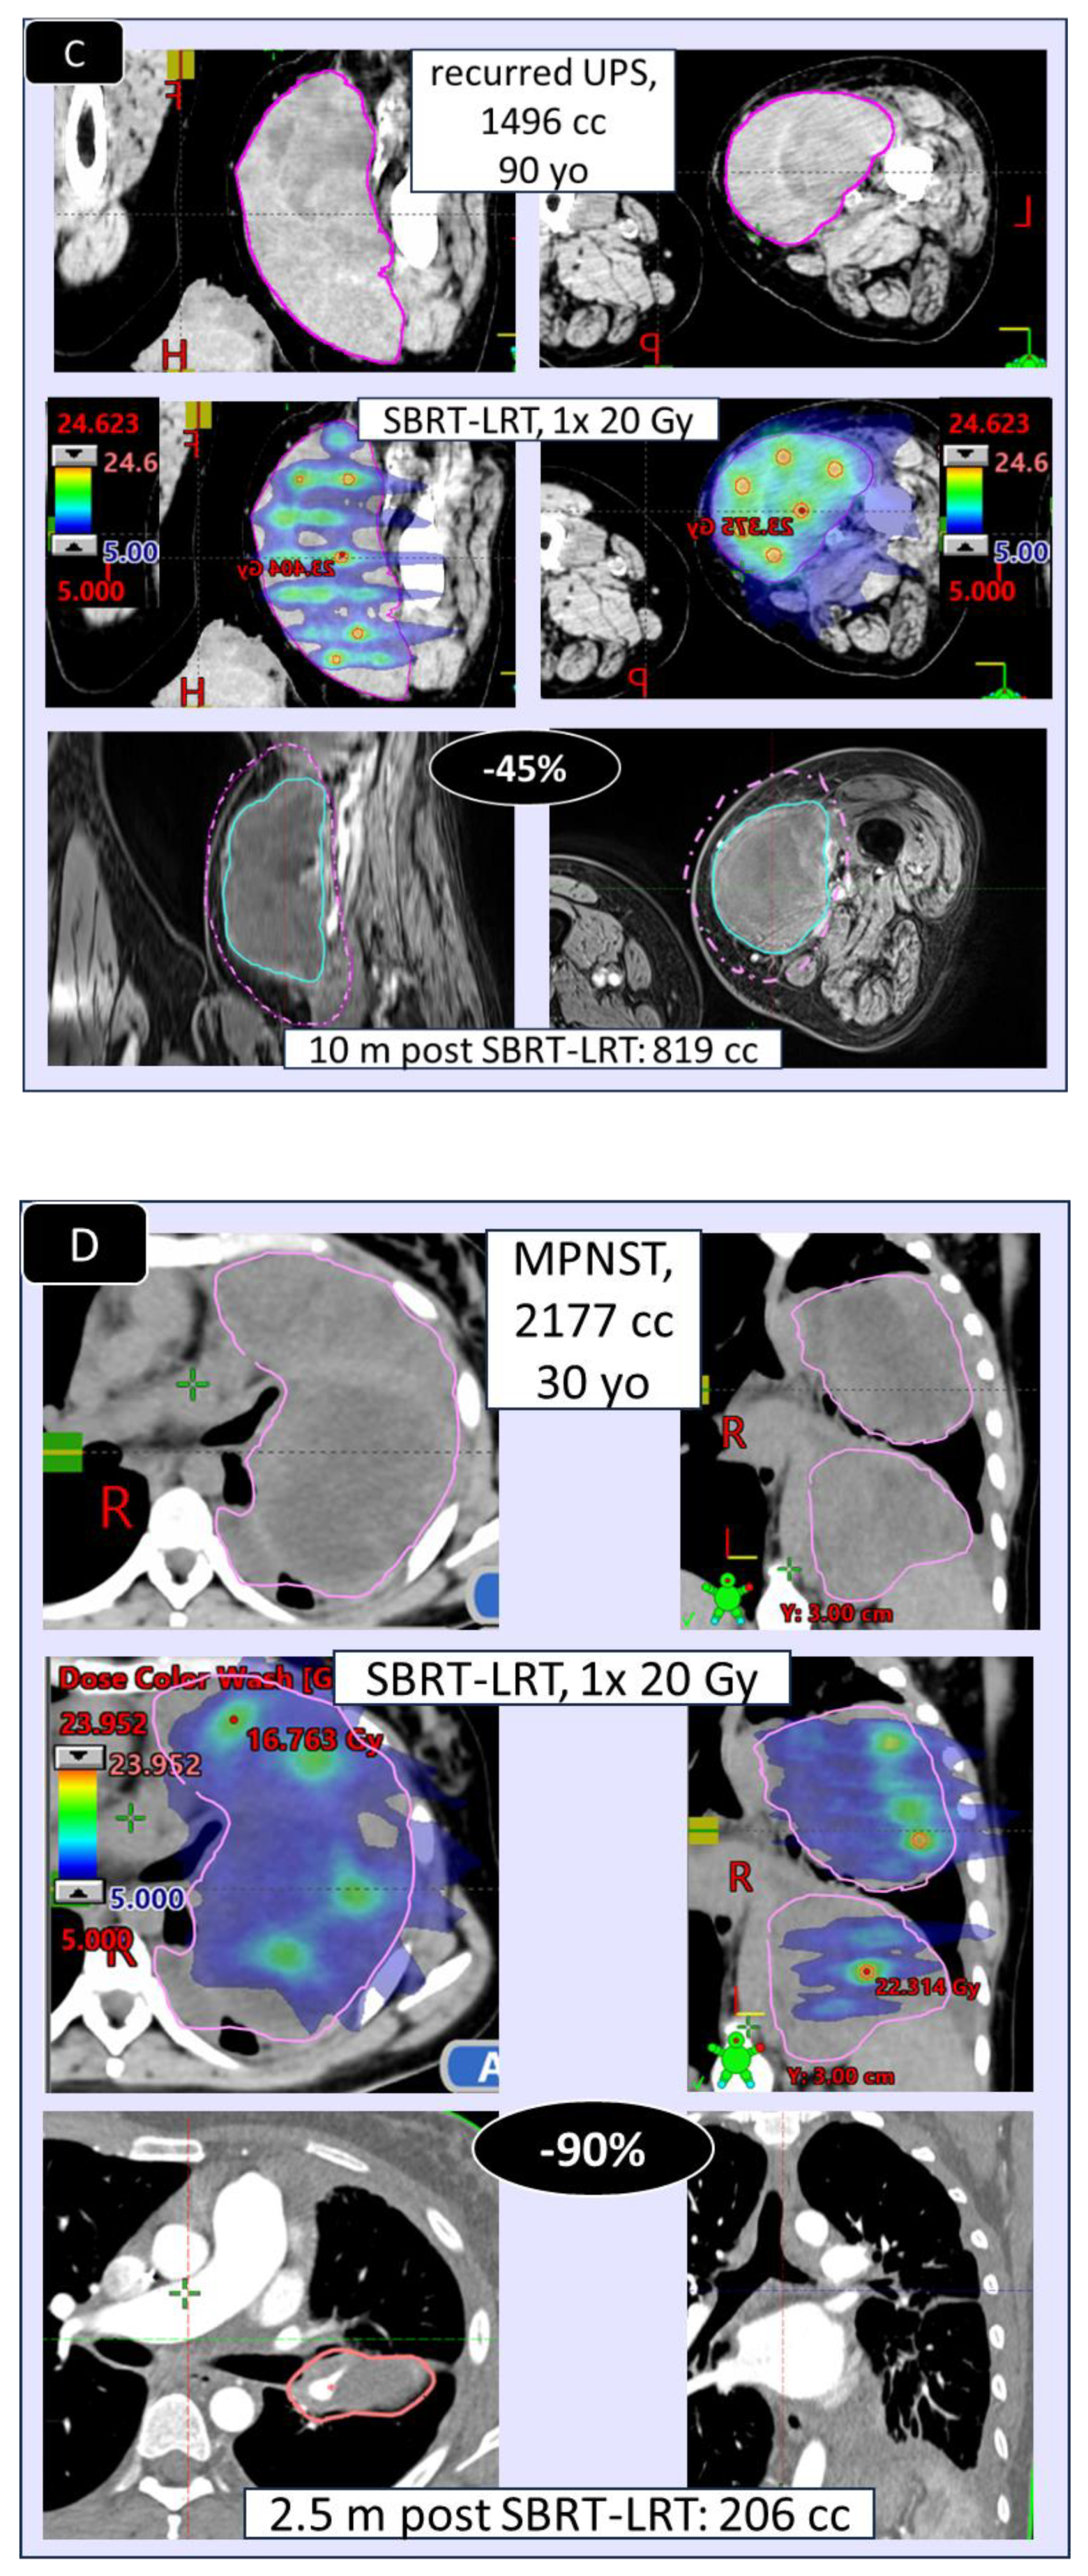

3.2. Radiologic/Volumetric Response, Table 5, Figure 2

| MLS | myxoid liposarcoma |

| UPS | undifferentiated pleomorphic sarcoma |

| MPNST | malignant peripheral nerve sheet tumor) |

| •EXTENT of shrinkage, % (mean/median (range) | 53/50 % (15-100) | 55/39 % (14-100) | - |